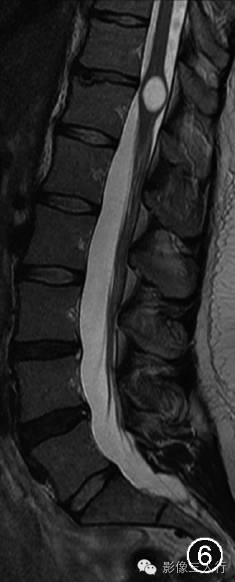

图4~7 男,45岁。腰椎MRI显示第五脑室是位于脊髓圆锥内且囊壁光滑的囊腔,囊腔内的脑脊液在矢状面T1WI上呈低信号(图4),在横断面T1WI上呈低信号(图5),在矢状面T2WI上呈高信号(图6),在横断面T2WI上呈高信号(图7)。所有图片均由加拿大渥太华大学渥太华医院Carlos Torres教授提供